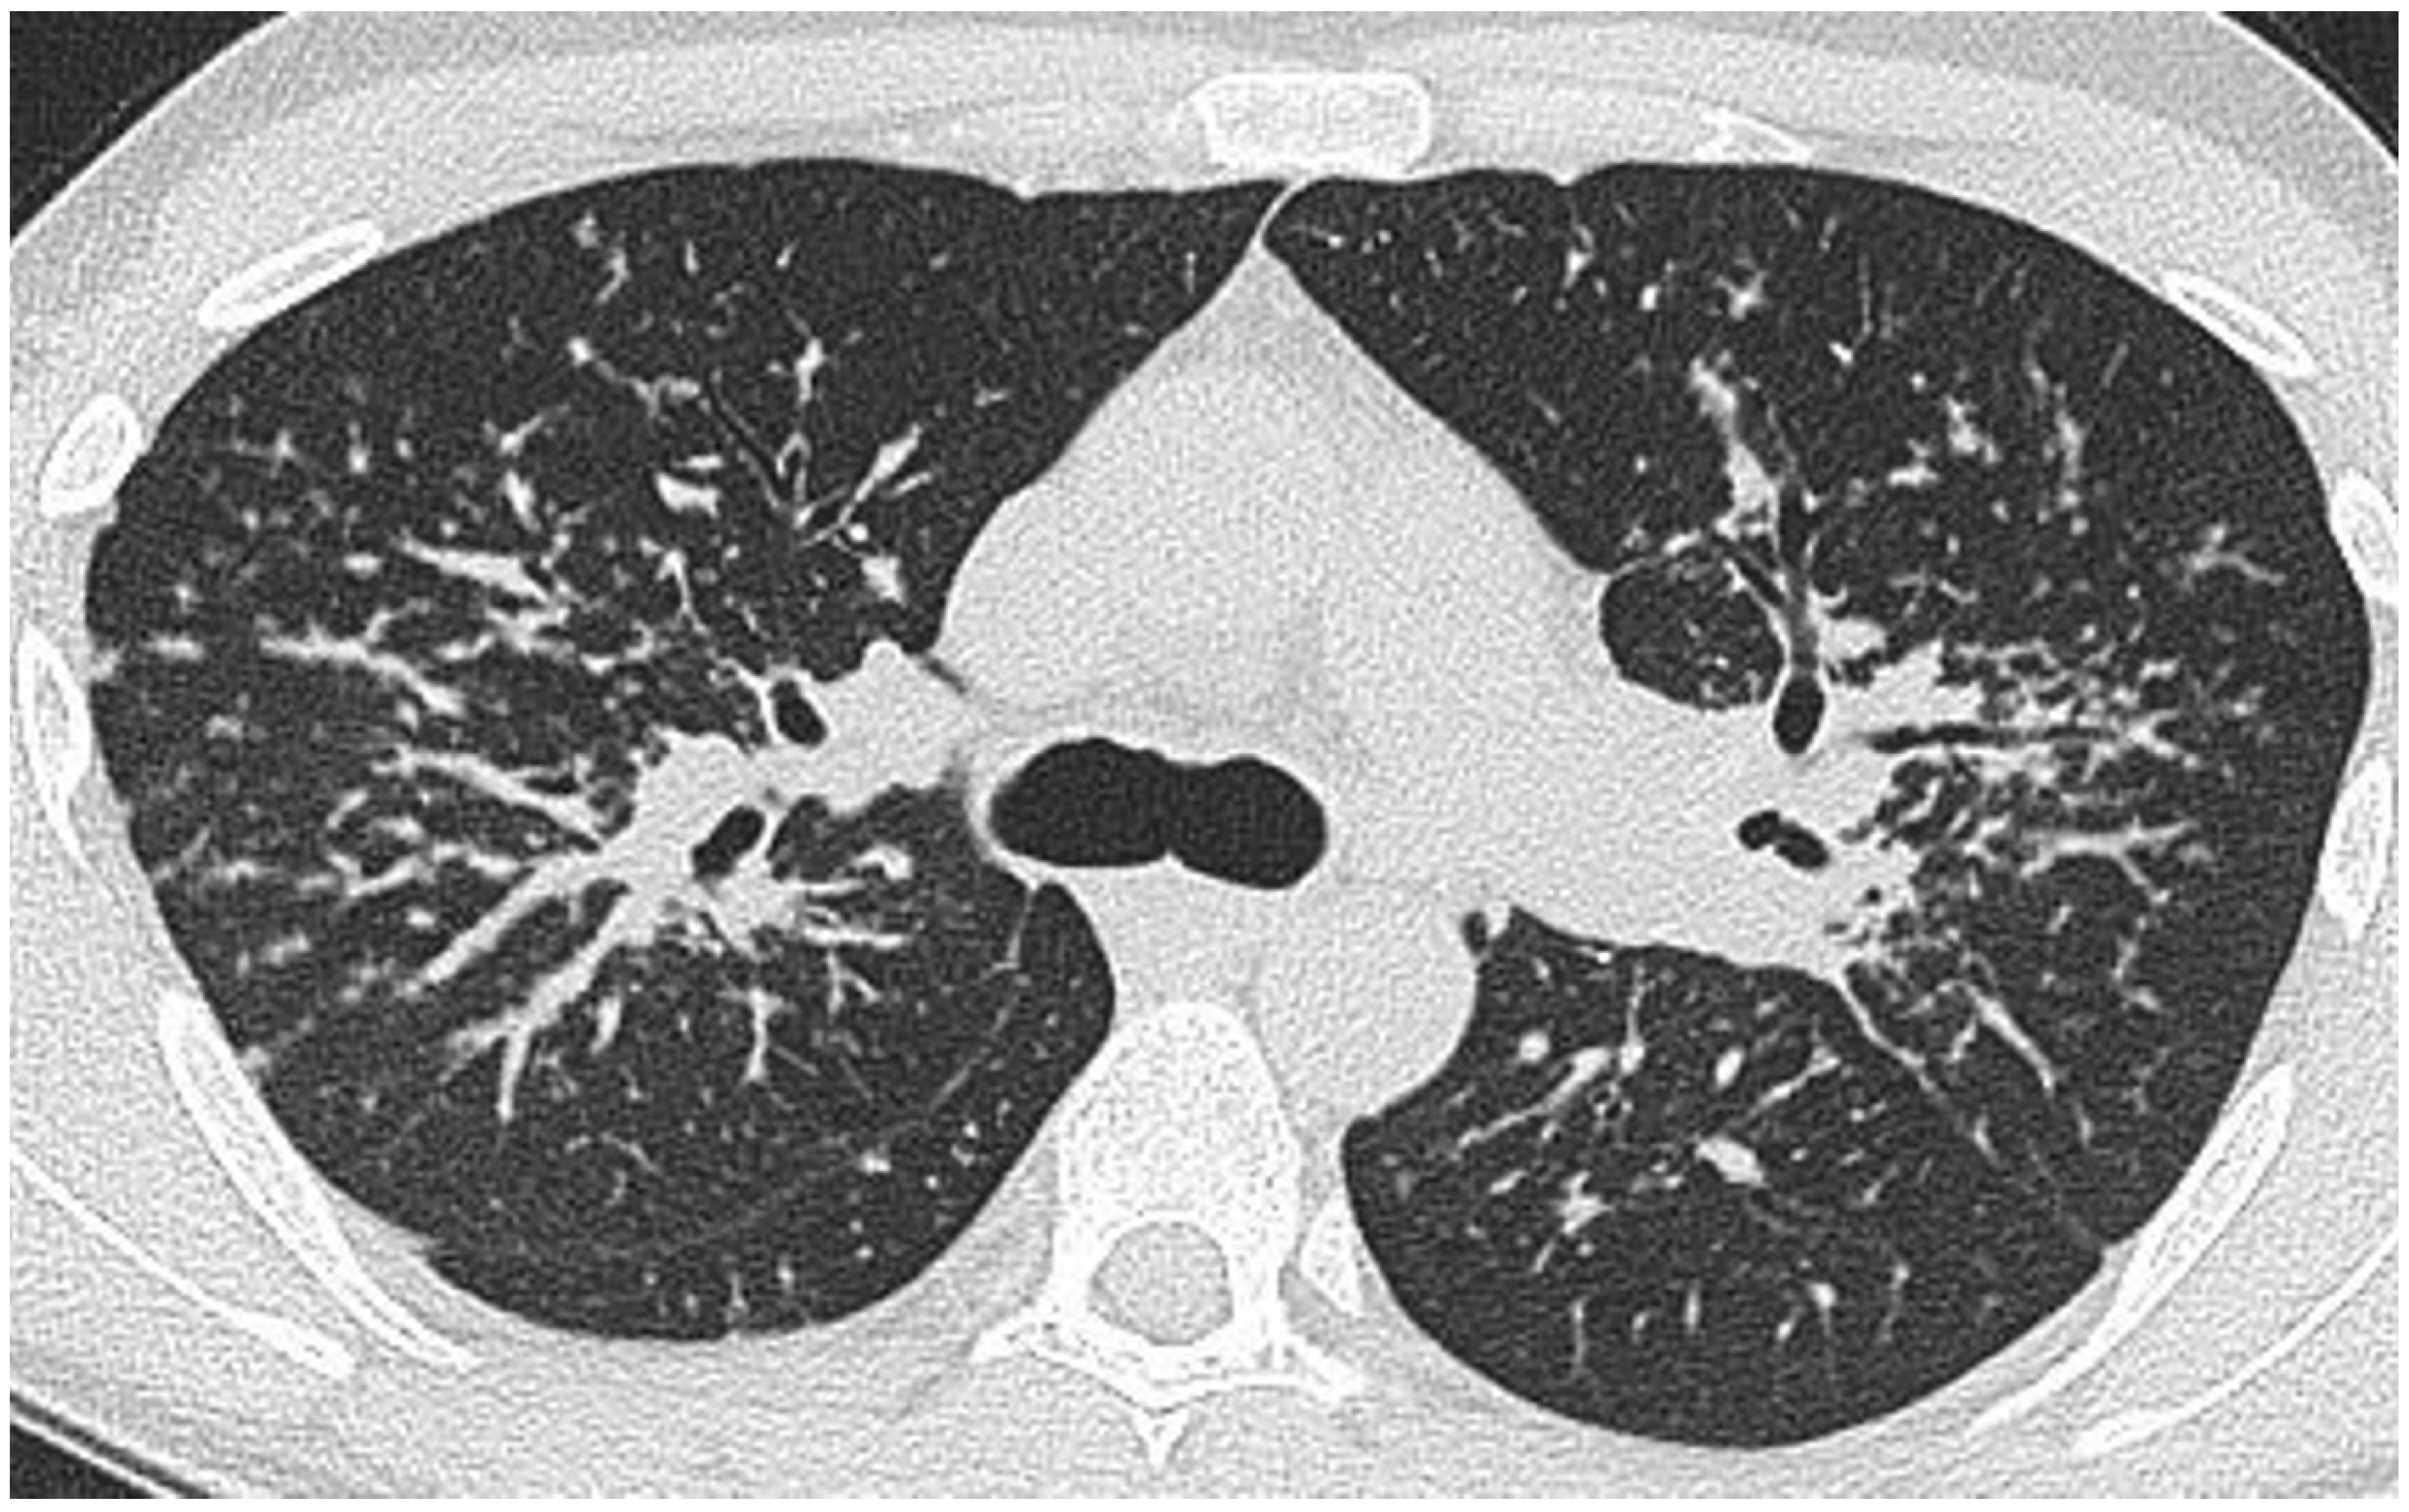

Lung nodules on CT are the most widely recognised and common CT manifestations of sarcoidosis [7,47,48]. In a small series of 45 patients with suspected or known sarcoidosis, nodules were present in 80% [7]. In a larger study of 95 patients by Remy-Jardin et al., a nodular pattern was present in 93% [49]. In the classical case, bronchocentric micronodules (measuring 1–3 mm in diameter), are seen in the mid and upper zones. Lung nodules, corresponding to aggregates of microscopic epithelioid granulomata [50], may be diffusely distributed throughout the lungs or, less frequently, localised to one or several focal areas. The predilection for the axial interstitium (i.e., surrounding bronchovascular bundles), accounts for the readily recognisable thickened, irregular perihilar and peribronchovascular appearance [48] (Figure 2). Irregular or nodular thickening of interlobular septa—mimicking lymphangitis carcinomatosa—is recognised but is rarely a dominant feature [51,52,53].

Figure 2.

CT at the level of the carina in the same patient as in Figure 1. There is a roughly symmetrical bronchocentric micronodular infiltrate. More centrally, there is dense parenchymal opacification caused by conglomeration of nodules around the bronchovascular structures.